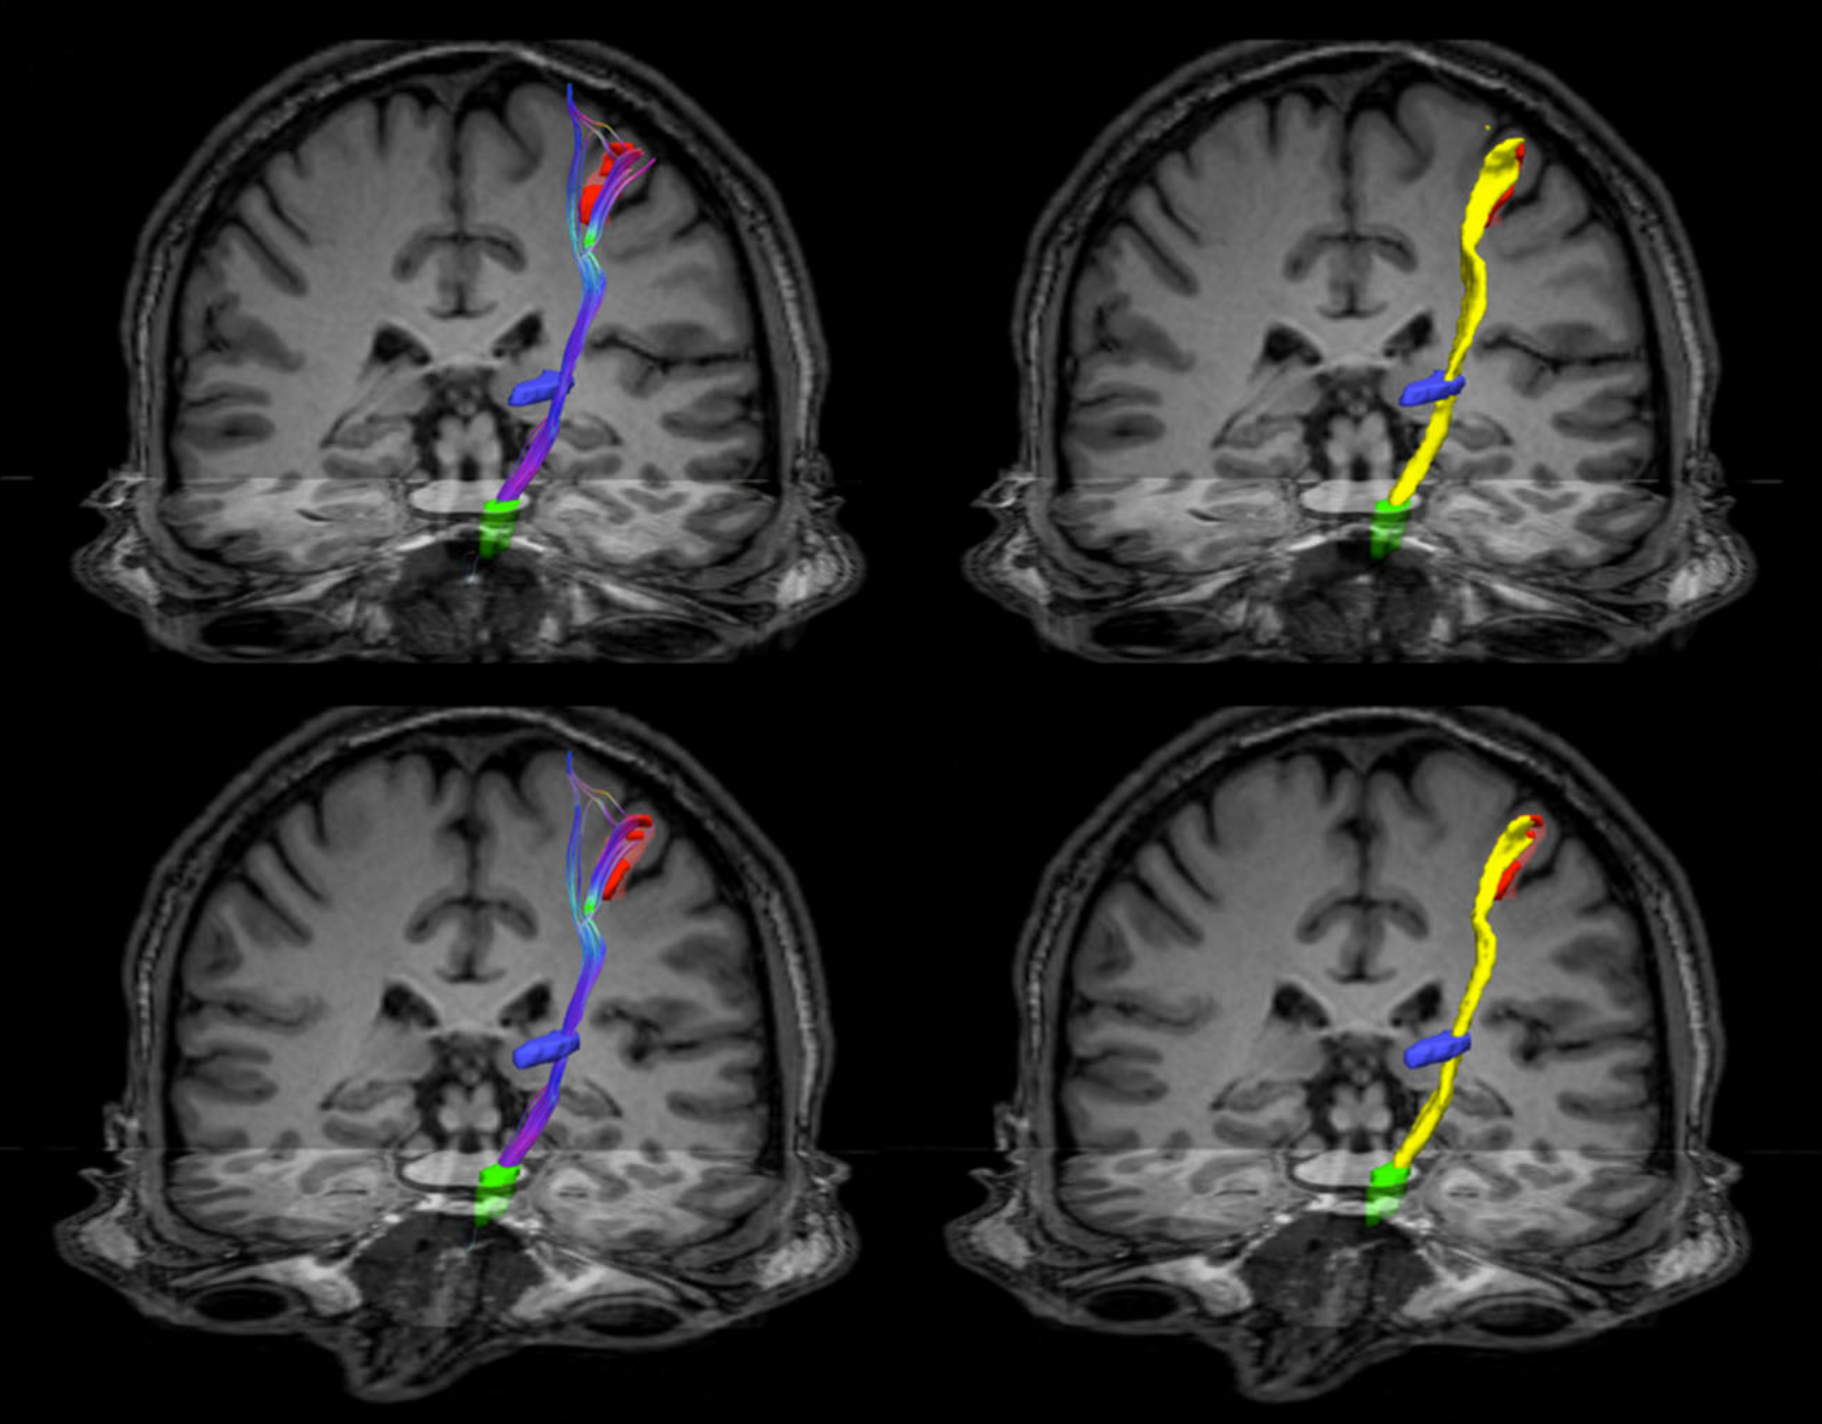

Neuroimaging is the process of generating images of the brain and is a powerful approach to gain a glimpse of the inner workings of the brain and its structure. Neuroimaging can refer to any methodology to captures pictures of brain; examples are MRI, CT scans, PET scans, fNIRS, among others. All provide information about a distinct feature of brain structure, function, or metabolism. In the lab, we focus mainly on MRI studies to gain insights about the function and structure of the brain. We employ diffusion MRI to generate maps of connectivity or of the microstructure of the brain. We also employ fMRI techniques to gain insights regarding the organizational principles of brain activity and dynamics. This toolbox allow us to gain a noninvasive view of the brain and obtain important information about the brain’s functional and structural reconfiguration in animal models of neuropsychiatric disorders and human subjects.